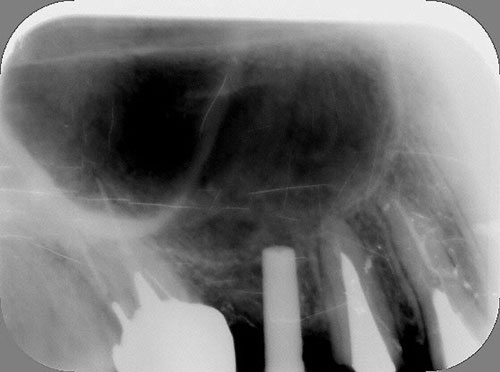

Mientras dichos movimientos ortopédicos se producen (período que supondrá otros seis meses), estudiamos los actos quirúrgicos a realizar en los cuatro implantes que pondremos. De acuerdo al estudio Desatascan realizado observamos tres situaciones diferentes: 1º-El Primer Molar Inferior Izquierdo, lo instalamos mediante Cirugía Minimamente Invasiva , con la aplicación de una Férula Quirúrgica Obtenida de los datos del scanner tratados con un programa de CMI (Cirugía Minimamente Invasiva), previa prueba en un modelo estereolitográfico, ya que la altura ósea era apenas de 9 mm. 2º- El Primer Molar Superior Derecho, se implantará mediante una ligera Elevación Atraumática (Trans alveolar) de Seno una vez logrado el espacio mesio distal necesario. 3º- El Incisivo Central Superior Derecho ausente, cuenta con un sustrato óseo prácticamente inexistente. El espesor de la tabla era de menos de 2 mm. Los caminos posibles a seguir para contar con una Rehabilitación de piezas independientes son dos: Optamos por esta segunda opción por ser menos cruenta y no necesitar de una zona dadora. Técnica esta que pondremos en práctica en dos etapas diferidas: 1º-Incisión horizontal palatinizada, incisiones peri rodetes gingivales e incisiones de descarga. Dilatación que comenzamos con dos incisiones de descarga sobre la cortical vestibular realizadas con disco. y el comienzo de la dilatación propiamente dicha mediante una hoja de bisturí, para luego seguir con un periostótomo . Recién después de alcanzada una cierta separación de la cortical vestibular de la palatina, empezamos con los dilatadores roscados. En este punto podríamos haber utilizado sin riesgos un Implante de 3,8 mm de diámetro, pero a fin de mejorar la estética del pilar emergente decidimos rellenar con material osteoconductor y osteoinductor (BiOss) y cubrir mediante membrana reabsorvible ( Bio Guide). 2º-Implantación seis meses después. Mientras se van cumpliendo los tiempos antes mencionados, y comprobamos reiteradamente la funcionalidad de la oclusión con los provisorios, tomamos impresiones definitivas y construimos primero el maxilar inferior, para definir en primer término la porción inferior de la Guía Anterior., y a nivel posterior Curvas y Microplanos. Para luego realizar los cuadrantes premolar- molar del superior: La espera de la regeneración ósea y sus tiempos pertinentes, más la espera de los tiempos de la implantación, nos obligaron a modificar las etapas del protocolo D.AT.O de manera de mantener la –D- mediante el sector superior de la GA. en provisorios, mientras fuimos resolviendo en forma definitiva los demás sectores. Ya pasados los meses necesarios para recrear un hueso adecuado en el área del Incisivo Superior Derecho, procedemos a resolver la implantación de dicha zona, observando que todo el esfuerzo dedicado al mismo había sido inútil, ya que la formación de hueso se produjo minimamente. Cuatro meses después tomamos impresiones del sector Antero Superior de la Guía Anterior, incluyendo el arrastre de un transfer . Seguimos modelando la encía con un nuevo juego de provisorios. Y se construye entonces el sector superior de la Guía Anterior. Se efectúa un control radiográfico a los 6 meses. Se ha intentado mostrar en esta Rehabilitación, que a pesar de las distintas circunstancias de cada paciente, siempre debemos tener en cuenta la necesidad de ejercer la DESOCLUSIÓN del caso como prioridad número uno, para luego perseguir la ALINEACIÓN TRIDIMENSIONAL de las arcadas y obtener así una OCLUSIÓN equilibrada. D.AT.O. ES EL PROTOCOLO QUE DEBEMOS SEGUIR EN TODA REHABILITACIÓN. BIBLIOGRAFÍA 1)William Mc Horris,B.S.,D.D.S. Oclusión. Con especial énfasis sobre :El rol funcional y parafuncional de los dientes anteriores. 2)Von Spee , Craff(Anatomista alemán, describió la curva de compensación de la articulación de molares y premolares).CURVA DE SPEE 1.89 3)Stuart,D.”Some aspects of the inervation teeth.”Procedings of Royal Society of Medicine.20:1675,19274)Muhleman,H. y Savdir,S”Tooth movility-its causes and significance”Journal of Periodontology ,36:153,Marzo ,Abril,1965. 4)Muhleman,H. Y Savdir,S”Toothmovility its causes and significance” Journal of Periodontology,36:153,marzo,abril,1965. 5-Oclusión y Diagnóstico en Rehabilitación Oral. 6-Anatomia Odontológica. 7-A contribution to the study of the movementes of the mandible. 8-Celenza F.W, Nadeskin J.F.,Oclusión.Situación actual. 9-D´Amico 10-Dawson P.E. 11-Huffman –Regenos. 12-Hobo S.-Takayama H.A. 13-Lucia V.O 14-Mc Horris. 15-Mc Horris. 16-Stuart C. 17-Vartan Veshnilian 18-Alvarez Cantoni H. AUTOR:Ratificación del Protocolo en Rehabilitación Bucal a pesar de las incidencias propias de cada caso clínico. A propósito de un caso.

Verificamos también el escaso ancho crestal, lo que nos obliga a utilizar dilatadores roscados y un osteótomo para elevar inicialmente la membrana de Schneider.

Esperamos seis meses antes de implantar.

No obstante pudimos implantar satisfactoriamente mediante un implante de 4.2 mm. de ancho y 14 mm. de largo, con una nueva R.O.G.

El implante se encontraba perfectamente según comprobaciones radiográficas y clínicas al sondeo.